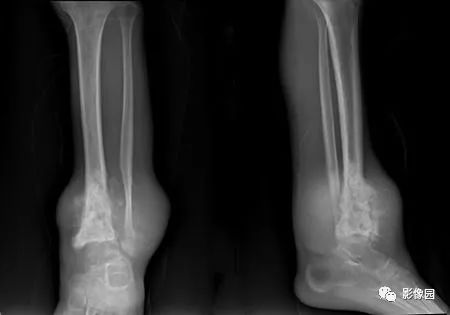

评论:前片X线示左胫骨下段及干骺端病变,髓腔内密度不均匀增高,内侧骨皮质可见骨质破坏,可见骨膜反应。CT示病灶内见多发斑片状肿瘤骨(黄色箭头),周围可见针状骨膜反应(红色箭头)。周围软组织肿胀。MRI示胫骨下段以长T1、长2信号为主的混杂信号影,未跨越胫距关节面,周围未见明显软组织肿块。周围软组织广泛片状长T1长T2信号影。复查X线示病变较前片明显进展,左侧胫骨远段及干骺端骨质破坏,周围可见针状骨膜反应及Codman三角(蓝色箭头)形成。相邻左侧腓骨下端、距骨滑车受累。

【结果】术中所见:左胫骨远端骨膜明显增厚,周围可见鱼肉样软组织,骨表面少许破坏,骨质条件差,进入骨髓腔后可见少许髓腔内少许白色软组织。切除骨膜、骨髓腔内组织送病检。

【病理】(左胫骨骨膜、左胫骨远端髓腔病灶)送检少许骨组织中见部分异型梭形细胞,考虑骨肉瘤。